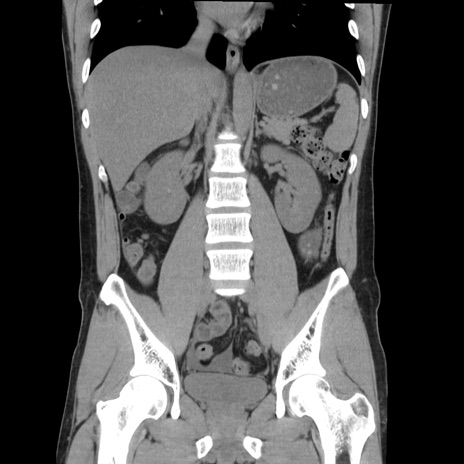

症例36(冠状断像)

【症例】20歳代 男性

【主訴】心窩部痛

【現病歴】今朝より上腹部痛あり。一旦軽快していたが再度出現したため救急要請。昨日夕に白身の魚を含む刺身を食べた。

【身体所見】BP 136/89mmHg、HR 74/min、BT 37.0℃、腹部:膨満、軟、心窩部に圧痛あり。反跳痛なし、筋性防御なし、腸雑音やや亢進あり。

【データ】WBC 17700、CRP 0.48